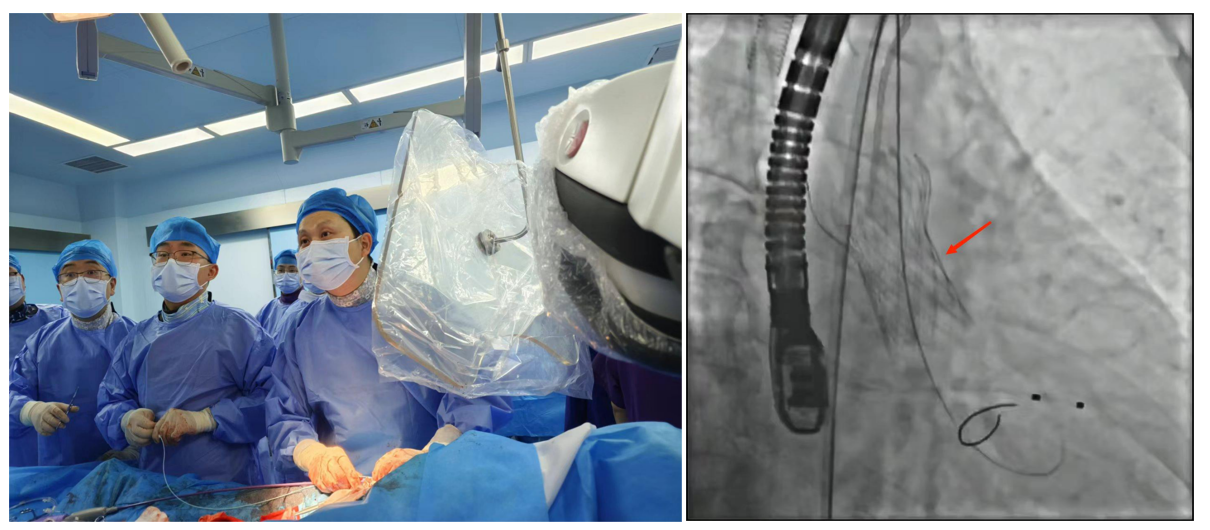

1.經皮冠狀動脈介入治療(PCI):是用心臟導管技術疏通狹窄甚至閉塞的冠狀動脈管腔,從而改善心肌血流灌注的一組治療技術。在血管嚴重狹窄或閉塞病變段放置支架或藥物球囊,以保證血管長期暢通,是冠脈介入手術的主流。

經皮冠狀動脈介入治療(PCI)